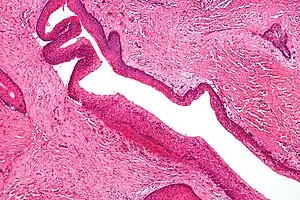

Familial adenomatous polyposis (FAP) is an autosomal dominant syndrome that greatly increases the risk of colorectal cancer. Around 1 in 8000 people will have this disease and it has approximately 100% penetrance. An individual with this disease will have hundreds to thousands of benign adenomas throughout their colon, which will in most cases progress to cancer. Other tumors increased in frequency include; osteomas, adrenal adenomas and carcinomas, thyroid tumors and desmoid tumors. The cause of this disorder is a mutated APC gene, which is involved in β-catenin regulation. Faulty APC causes β-catenin to accumulate in cells and activate transcription factors involved in cell proliferation, migration, differentiation and apoptosis (programmed cell death).[17][18][19]